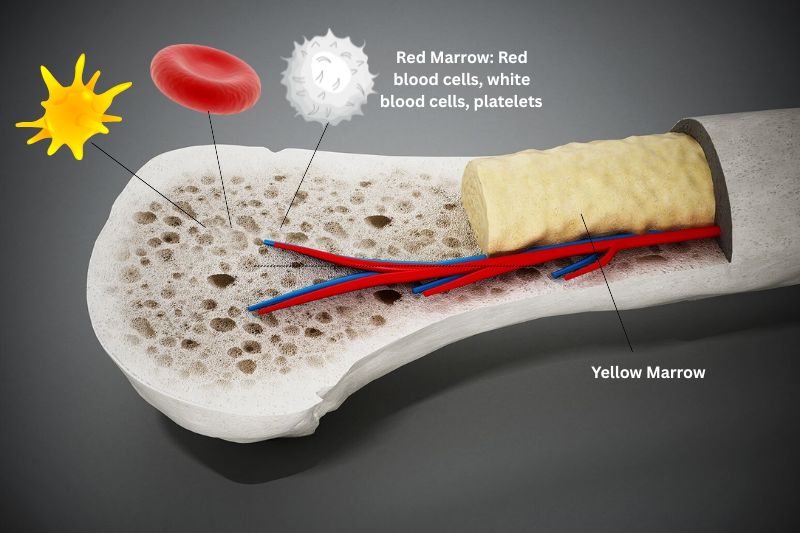

Bone marrow is the soft, spongy tissue found in the centre of bones. It is filled with blood vessels and comprises two main parts: Red marrow and yellow marrow. Red marrow contains stem cells that develop into red blood cells, as well as white blood cells and platelets. Yellow marrow is mainly fat and contains stem cells that become cartilage, fat or bone cells. When people roast marrow, they consume mostly the yellow marrow. The femur and shank bones from a beef cow are commonly used for roasting.

Bone marrow plays a vital role in your body. As your body’s ‘blood factory’, it could be said that bone marrow is keeping you alive. Red blood cells carry oxygen around the body, while white blood cells fight infection. Without platelets, your blood doesn’t clot, and you can’t stop bleeding.